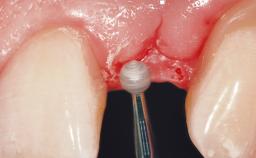

Late Placement of an Implant in a Maxillary Left Central Incisor Site

A 36-year-old female patient was referred for the replacement of the upper left central incisor (tooth 21), which had fractured. Although the tooth had been asymptomatic for many years, the crown began to loosen, at which time she presented to her dentist for an assessment. Teeth 21 and 22 had both been endodontically treated many years previously. She was a healthy individual and a non-smoker.

Bone Augmentation Horizontal|Staged

Augmentation Materials Xenogenous|Membrane

Bone Volume Deficient horizontally, requiring prior grafting